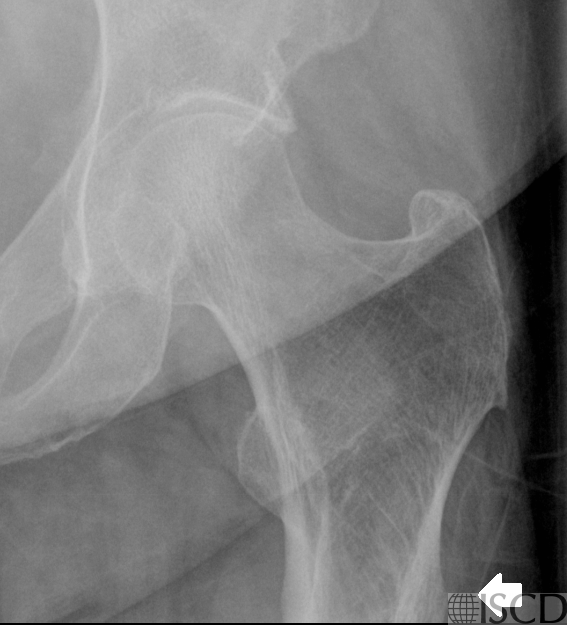

Figure 1A: Left hip DXA, arrow shows bony protrusion from the lateral cortical subtrochanteric femur.

Figure 1B: X-ray left hip shows bony exostosis from the lateral cortical subtrochanteric femur.

Left hip DXA image shows bony protrusion from the lateral cortical subtrochanteric femur. Periosteal stress reaction from an atypical femur fracture (AFF) might be considered, but the patient had received no anti-osteoporosis therapy, there were no symptoms and there was no endosteal reaction. Further review shows a history of multiple hereditary exostoses, as seen on x-ray for the left hip and knees.

This highlights the importance of clinical correlation and imaging review before diagnosing an AFF — there is always a differential to consider.